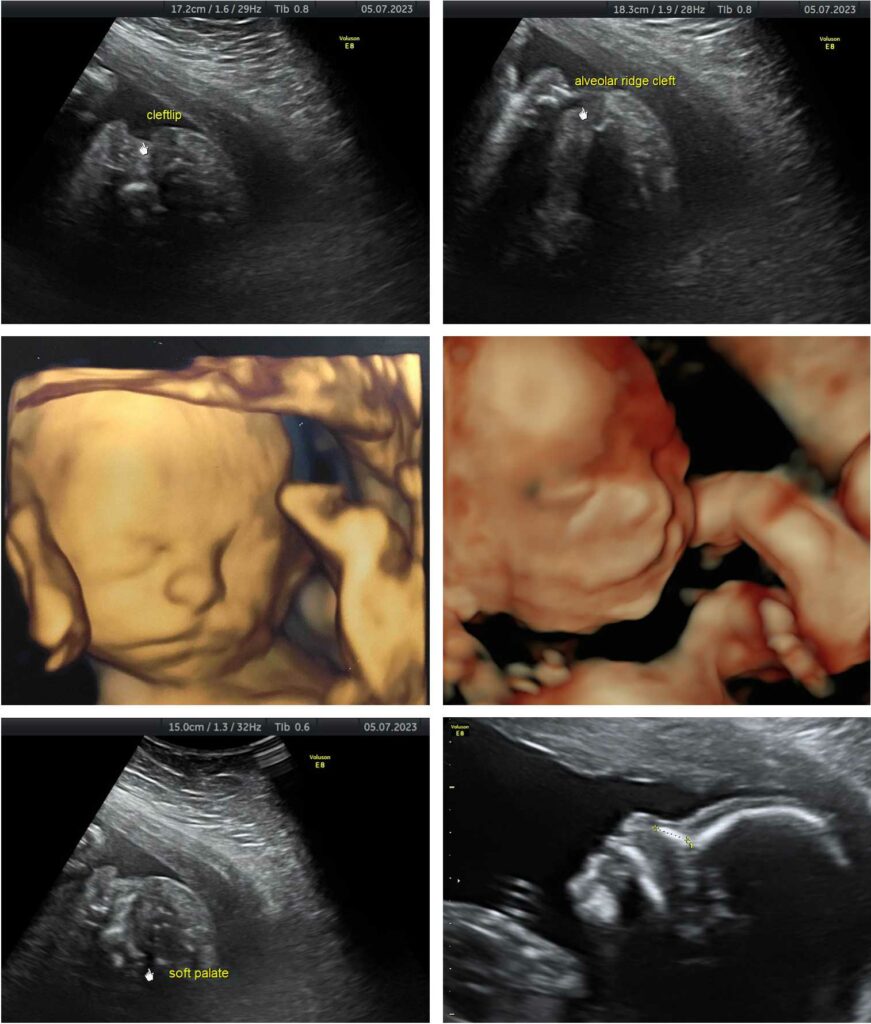

Η εξέλιξη της ιατρικής τεχνολογίας δίνει τη δυνατότητα να διαγνωστεί η ύπαρξη σχιστίας από την εμβρυική περίοδο με τον υπερηχογραφικό έλεγχο.

Εικόνες με υπερηχογράφημα σε έμβρυο με σχιστία